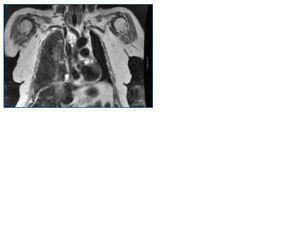

Enferma de 72 años que fue incluida en programa de hemodiálisis periódicas en abril de 2004 por enfermedad renal crónica secundaria a nefropatía diabética. Desde su inclusión en programa tuvo muchos problemas de acceso vascular. Inicialmente se colocó un catéter tunelizado yugular derecho. En mayo de 2004 se realizó fístula arteriovenosa braquiocefálica en miembro superior derecho que se trombosó precozmente. Tras un estudio vascular se consideró inviable la realización de una nueva fístula o prótesis. En mayo de 2005 por disfunción del catéter se inició tratamiento anticoagulante oral; en una angiorresonancia (fig. 1) se observó una estenosis de vena yugular interna derecha y cava superior. Se realizó dilatación de cava superior y colocación de catéter tunelizado a través de yugular derecha con la punta a nivel de cava inferior, que permitió continuar en el tratamiento de hemodiálisis.

Figura 1.